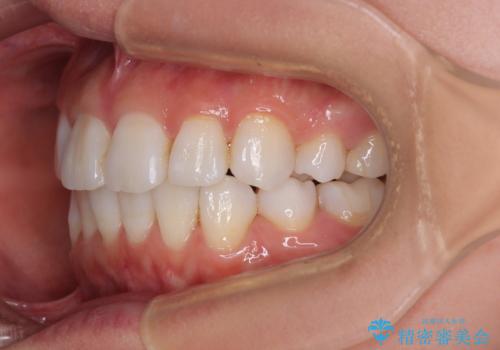

矯正治療の後戻り インビザラインで短期間矯正治療

- 上下前歯の後戻りを気にして来院された患者様です。

インビザラインでの治療を希望されていて、デコボコの程度が中等度であり、安価なパッケージにて対応可能と判断されたため、インビザライン・モデレートを用いて矯正治療を行うこととしました。

インビザライン・モデレートは、製作できるアライナーの枚数に制限があるため、移動可能な量に限りがあるものの、インビザライン・ライトよりも枚数が多いため、幅広い症例に対応可能です。